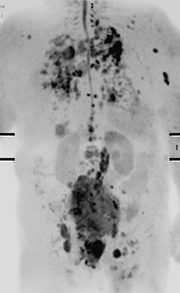

Ingeniaおける静磁場均一性の向上とdS-SENSEによるSENSEの高倍速化は,EPI撮像特有の磁化率アーチファクトやケミカルシフトアーチファクトを低減することが可能となるため,特にDWIにおいてその威力を発揮する。例えば,従来の全身DWI撮像は,撮像範囲を考えるとコロナル断面での撮像が適しているにもかかわらず,アーチファクトを考慮してアキシャル断面で撮像されていた。しかし,マグネットの静磁場均一性の向上,dStreamによるSNR向上,そして,dS-SENSEによるSENSE展開精度の向上によって,SENSEファクタ5を用いたダイレクトコロナルDWIのトライアルが実際にスタートしている。図4に,ダイレクトコロナルによる2スタック全身DWIの画像を示している。従来のように,アキシャル撮像で得られた画像をコロナル断面でMPR再構成を行う場合と異なり,ダイレクトコロナル撮像で得られた画像には信号の不連続が認められない。また,5倍速という高SENSEファクタを使用しても,画像中央部に顕著なノイズ成分は認められず,SENSEの展開エラーも確認できない。これらの結果は,いままで不可能とされたコロナルでのDWIを可能とし,臨床検査の内容と質を大きく変えていく可能性を示唆している。